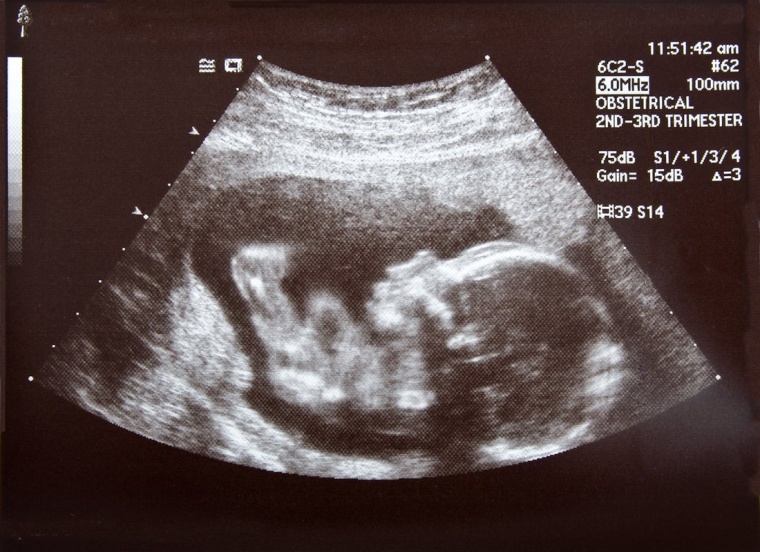

Von Fruchtbarkeitsuntersuchungen über Social Freezing – das Einfrieren von Eizellen für eine mögliche spätere Befruchtung – bis zu sämtlichen Kinderwunschbehandlungen wie Insemination (IUI), In-vitro-Fertilisation (IVF) oder intracytoplasmatische Spermieninjektion (ICSI) deckt das Zentrum das gesamte Spektrum der Reproduktionsmedizin ab. Die neuen Räumlichkeiten bieten dabei noch mehr Platz für eine individuelle Versorgung und Behandlung der Patientinnen.